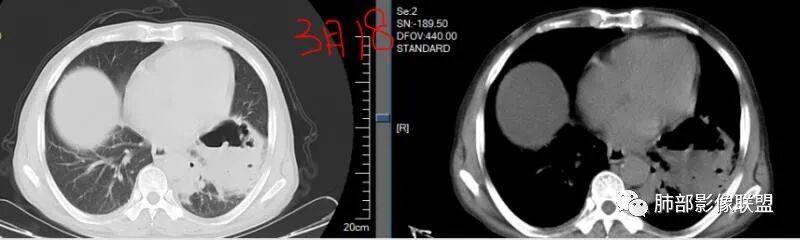

3.五天后及十三天后病灶变化明显,实性密度影吸收缩小,边界趋于清楚,显示多空腔。

3.金黄色葡萄球菌临床中毒症状明显,常寒颤高热起病,血源性感染者常有皮肤脓肿、伤口感染、蜂窝织炎、化脓性骨髓炎等等。病情变化快,影像进展迅速,短期内(如一两天内)迅速出现的有张力的菲薄气囊影,或多发成串分布的,尤具特征性!较之其他感染,短期内易出现脓胸。本例上述特征似乎不明显。

4.肺炎克雷伯杆菌肺炎病灶也易形成脓腔。本例患者未出现典型金葡感染影像学特征,患者临床表现相对“逍遥”缓慢,结合实验室检查,更符合肺炎克雷伯杆菌肺炎。